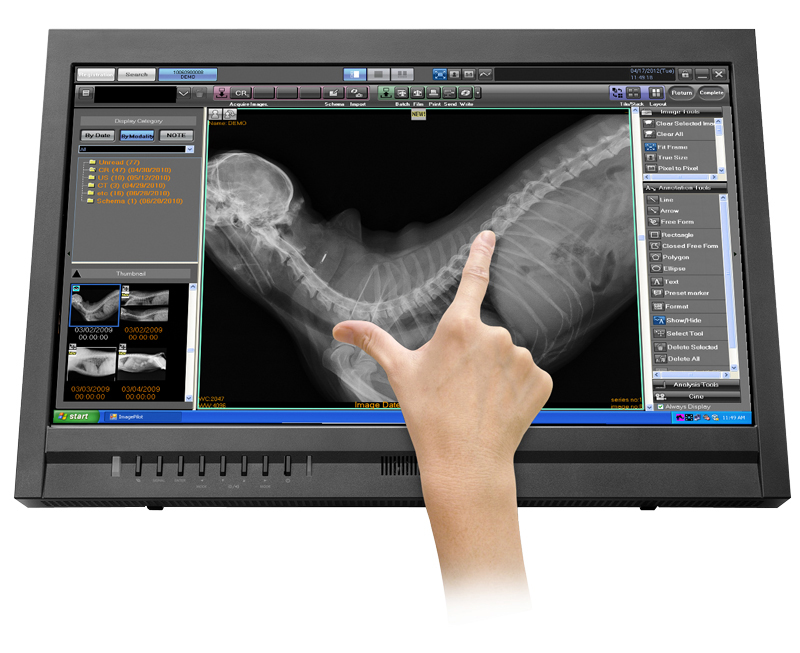

Tool completo analisi immagini

Il sistema ImagePilot include tutti gli strumenti necessari per lo studio diagnostico delle radiografie. I comandi di analisi delle immagini permettono una gestione rapida e flessibile di tutti i parametri di esposizione dell’immagine e ti supportano attivamente nella fase di diagnosi della patologia in esame.